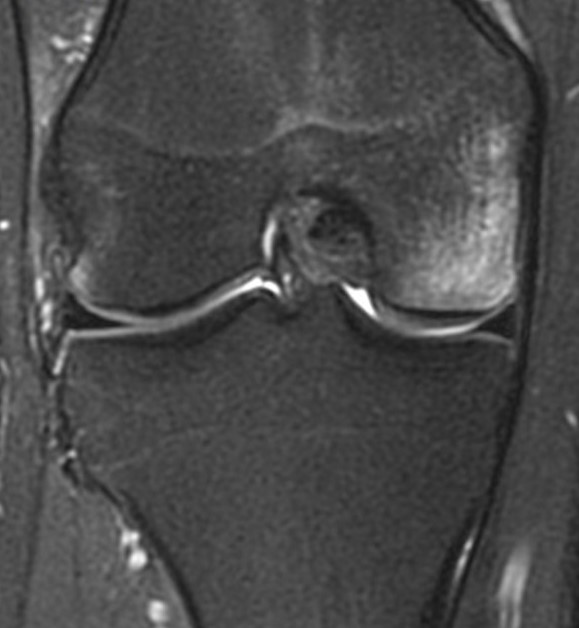

From Rachael Gordon, A neuron who reads TMJ’s. Great points! Phil, I have seen the pterygoid atrophy. Mostly in patients with head and neck CA who have had XRT. This is better seen on axial images, which can be worth adding, especially if the patient has trismus. I have seen the disc tear like this […]